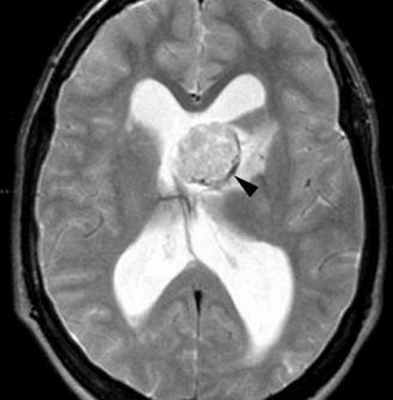

МРТ головного мозга. Туберозный склероз. Гигантоклеточная внутрижелудочковая астроцитома (стрелки). Прорастание в хвостатое ядро. Окклюзия отверстия Монро. Т2-зависимая, Т1-зависимая и Т1-зависимая с контрастированием аксиальные МРТ.